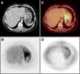

Increased carbohydrate metabolism